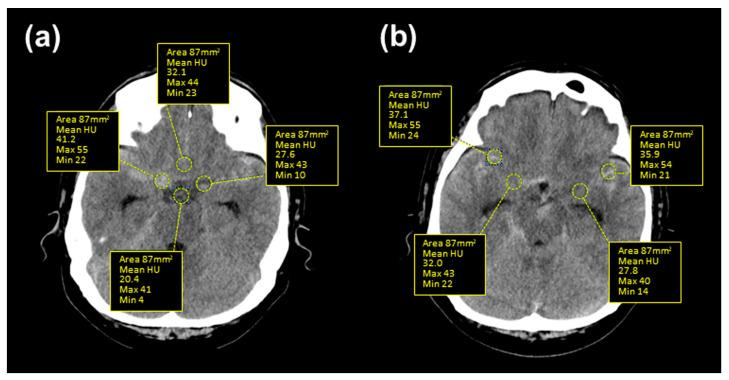

Clazosentan prevents vasospasms after aneurysmal subarachnoid hemorrhage (SAH). However, clinical data on patients with SAH with ruptured vertebral artery dissecting aneurysms (VADAs) are limited. We report the case of a 49-year-old male patient with mild-grade (WFNS grade 1) thick and diffuse (modified Fisher grade 3) SAH who underwent endovascular trapping of a ruptured VADA, resulting in a poor functional outcome with a modified Rankin Scale score of 4 due to severe symptomatic vasospasm refractory to clazosentan, requiring repeated rescue endovascular therapies and chronic communicating hydrocephalus. A retrospective analysis of the clot density in the basal and Sylvian cisterns, assessed by the Hounsfield unit (HU) values of serial CT scans, in this patient showed persistent higher values, distinct from another VADA case that showed a decline in HU values with a good clinical course. These results imply the limited effectiveness of clazosentan in cases of thick and diffuse SAH after a ruptured VADA, even in good-clinical-grade patients treated with less invasive modalities. The HU values may become a simple quantitative marker for predicting symptomatic vasospasms and chronic hydrocephalus.

克拉生坦可预防蛛网膜下腔出血(SAH)后的血管痉挛。然而,关于破裂椎动脉夹层动脉瘤(VADA)的 SAH 患者的临床数据有限。我们报告了一例 49 岁男性患者,其为轻度(WFNS 分级 1)厚且弥漫(改良 Fisher 分级 3)SAH,接受了破裂 VADA 的血管内夹闭术,由于严重的症状性血管痉挛对克拉生坦无反应,需要反复进行血管内救援治疗和慢性交通性脑积水,导致功能预后不良,改良 Rankin 量表评分为 4。对该患者的基底池和外侧裂池的血栓密度进行回顾性分析,通过连续 CT 扫描的亨氏单位(HU)值评估,发现持续存在较高的 HU 值,与另一例 HU 值下降、临床过程良好的 VADA 病例不同。这些结果表明,即使在接受侵袭性较小的治疗方式的良好临床分级患者中,克拉生坦在破裂 VADA 后发生厚且弥漫性 SAH 时的疗效有限。HU 值可能成为预测症状性血管痉挛和慢性脑积水的简单定量标志物。

Hounsfield unit as a predictor of symptomatic vasospasm and hydrocephalus in good-grade subarachnoid hemorrhage treated with endovascular coiling.亨斯菲尔德单位作为血管内栓塞治疗的良好分级蛛网膜下腔出血患者症状性血管痉挛和脑积水的预测指标。

Quant Imaging Med Surg. 2023 Oct 1;13(10):6627-6635. doi: 10.21037/qims-23-355. Epub 2023 Aug 14.